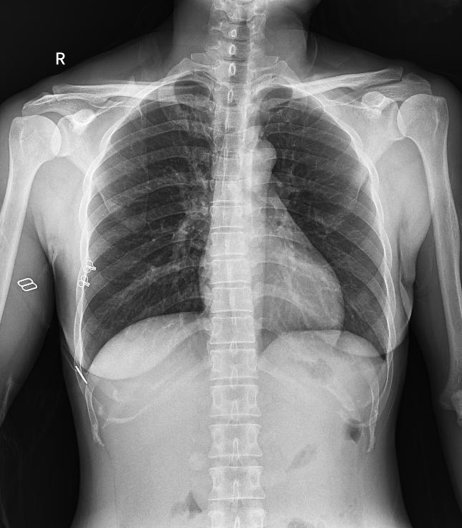

普利德醫療自主研發(fā)的新一代數字化X線(xiàn)透視攝影系統,可應用于DR攝影、數字透視、數字造影以及可視化精準DR拍片等多種臨床X線(xiàn)檢查領(lǐng)域。

拉伸自如:SID電動(dòng)拉伸,最長(cháng)可延伸至1.8米,滿(mǎn)足放射科室各種拍片距離的需求。如:GBZ 70-2015職業(yè)性塵肺病的診斷標準中對胸片拍片距離1.8米的要求。

● 高效動(dòng)態(tài)平板技術(shù),圖像不會(huì )有幾何畸變,提供高分辨率和精確的圖像,為醫生臨床診斷提供精準依據;

● 17*17英寸的超高清像素動(dòng)態(tài)平板探測器,更大的視野范圍,無(wú)需移動(dòng)即可觀(guān)察整個(gè)動(dòng)態(tài)過(guò)程,避免拖尾、噪聲對圖像的影響;